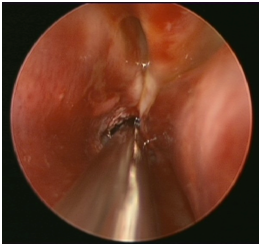

In this technique, the surgeon introduces a 2.9mm endoscope through the nasal cavity. Identification of choanal atresia is then performed. Using a straight suction, a puncture is performed anterior-inferiorly close to the vomer bone of the nasal septum (Figure 2A). Visualization of adenoid pad in the nasopharynx assures proper puncture through atresic palte and not into soft palate (false passage). The opening is then enlarged using a drill or shaver depending on the thickness of the atretic plate (Figure 2B, Figure 2C). A mucosal flap is usually not possible to preserve by the end of the procedure. The other choana atresia side is addressed similarly. Lastly, the vomer is removed using a backbiter forceps. Two size 3.5 endotracheal tubes are used one in each side and tied together anteriorly using a sub-labial suture for fixation to avoid collumellar pressure. The stent are removed in the clinic six weeks later.

A                                                                      B                                                            C

Figure 2 A) Transnasal endoscopic puncture using a straight suction for right choanal atresia. B) Shaver blade enlarging the puncture opening. C) Final result.